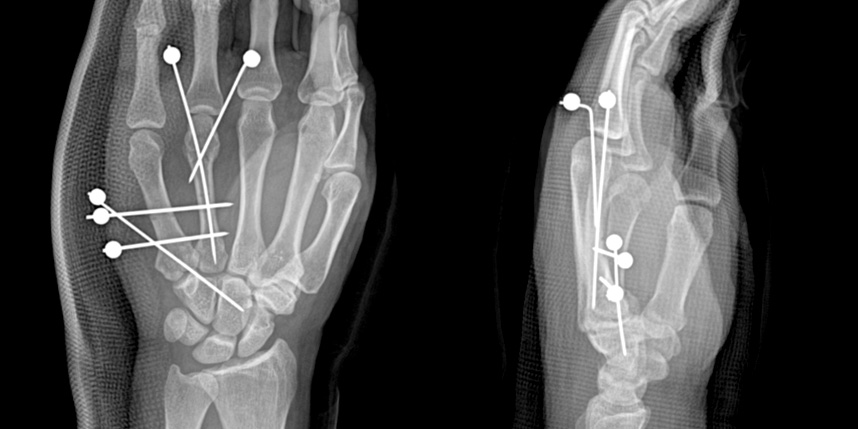

손가락 골절

골절이 심하지 않은 경우에는 깁스로 고정해서 유합을 시킬 수 있으나, 정도가 심한 경우에는 손,발목 골절 수술을 진행할 수 있습니다.

골절은 정확하게 골절편을 잘 맞추고 고정하는 것이 중요합니다. 특히 관절면을 잘 맞추는 것이 중요합니다.